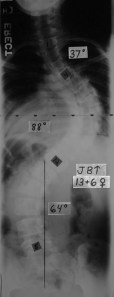

This was my spine (I was around thirteen and a half) BEFORE spinal surgery. See the “S” shape? That’s an S-curve from scoliosis. Doctors aren’t sure what causes most cases of scoliosis. Maybe, with more research, they’ll soon have answers to that question.

So, it’s pretty obvious that my spine was waaaaay out of shape. Even after years of wearing various back braces and doing different exercises–it looked like that. My spine was so twisted that it was pressing on my heart and lungs. Not good, you know?

That scary x-ray led my doctor at Shriners to do this…